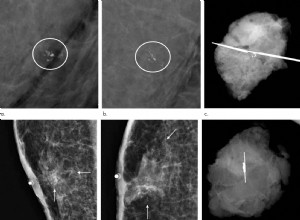

Dépistage du cancer du sein chez les hommes à haut risque : un diagnostic précoce qui sauve des vies